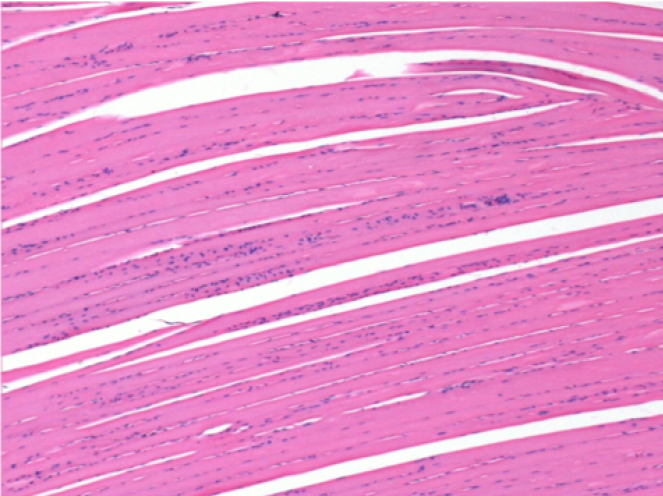

7 mesi dopo Iniezione di Endopeel

Scatola Nr 5

7 mesi (Giorno210) dopo iniezione IM di 0.1ml di Endopeel nel muscolo pretibiale destro ( Dx).

Restitutio ad integrum completo dopo 7 mesi

Sx : Controllo-100x-Giorno210

Dx:100x-Giorno210

Sx :Controllo 50x-Giorno210

Dx:50X-Giorno210